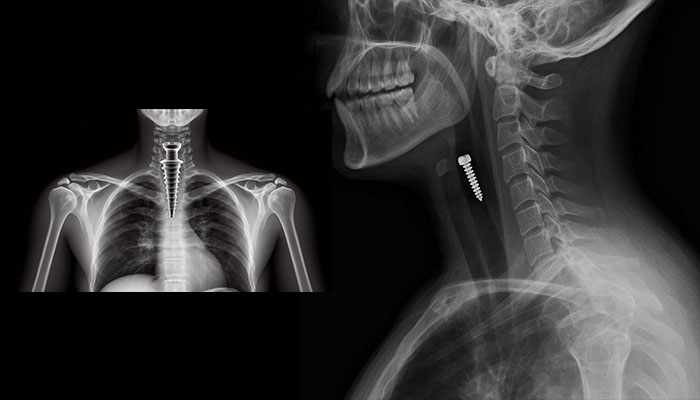

پس از قورت دادن پیچ یکی از اجزای ایمپلنت دندان، نخستین اقدام پزشک تعیین دقیق محل قرارگیری آن است. این مرحله معمولاً با استفاده از تصویربرداری انجام میشود:

- رادیوگرافی ساده (اشعه ایکس): رایجترین و ابتداییترین روش؛ تیتانیوم پیچ بهخوبی در اشعه ایکس دیده میشود.

- رادیوگرافی قفسه سینه: برای اطمینان از عدم ورود پیچ به مجاری تنفسی (نای یا ریهها).

- رادیوگرافی شکم: برای دنبال کردن مسیر پیچ در دستگاه گوارش؛ گاهی نیاز است چند تصویر در زمانهای مختلف گرفته شود تا حرکت پیچ مشاهده شود.

- سیتیاسکن: در صورتی که رادیوگرافی اطلاعات کافی ارائه ندهد یا احتمال آسیبهایی مانند سوراخ شدن وجود داشته باشد، سیتیاسکن تصاویر دقیقتری از موقعیت پیچ و بافتهای اطراف فراهم میکند.

- آندوسکوپی: اگر پیچ در مری یا معده گیر کرده باشد و نیاز به خارج کردن سریع آن باشد، آندوسکوپی بهترین گزینه است. در این روش، یک لوله نازک و منعطف مجهز به دوربین از دهان وارد مری و معده میشود و پیچ قابل مشاهده و در صورت امکان با ابزارهای مخصوص خارج میگردد.